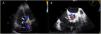

On initial assessment his complete blood cell count and serum electrolyte levels were within normal limits. NT-proBNP level was 5030 pg/ml. There was no evidence of infective endocarditis. Chest radiography showed an increased cardiothoracic ratio with pulmonary vascular congestion. Transthoracic echocardiography revealed normal left ventricular function and normal functioning of the prosthetic aortic valve, dilatation of the right chambers with right ventricular systolic dysfunction (gradient between right ventricle and atrium of 40 mmHg), and a continuous color-flow jet from the aorta toward the right ventricular cavity (Figure 1A). Transesophageal echocardiography (TEE) confirmed the existence of a shunt between the aorta (at the level of the native right cusp) and the right ventricle (immediately above the insertion of the tricuspid annulus) (Figure 1B). It also ruled out infective endocarditis behind this abnormal communication and showed a well-seated prosthetic valve with no vegetation, prosthetic abscess, or aneurysm in the aortic root.

After discussion with the hospital's heart team and risk-benefit assessment, we decided that the surgical risk of reoperation was high and the patient was proposed for percutaneous closure. The procedure was performed under local anesthesia, with two arterial accesses (right radial 5F and femoral 6F) and one venous access for introduction of the ICE probe (right femoral vein, 8F). The ICE probe (ACUSON AcuNav ultrasound catheter, Siemens, Mountain View, CA) was placed in the right ventricle with optimal visualization and alignment with the fistula (Figure 2A). A 5F pigtail catheter was positioned in the ascending aorta, and the fistula's position was confirmed by angiography (Figure 3A). A 5F MP1 catheter was advanced through the right femoral artery, crossing the fistula into the right ventricle (Figures 2B and 3B). Through the MP1 an 0.035“Amplatzer guidewire was positioned in the right ventricle and the 5F diagnostic MP1 was exchanged for a 6F MP1 guiding catheter. The percutaneous closure device, a 6 mm Amplatzer Vascular Plug II (AVP) (Abbott, Chicago, IL), was then implanted (Figures 2C and 3C). ICE confirmed the correct positioning of the device, with minimal residual flow, and excluded interference with neighboring structures (Figures 2D and 3D). There were no complications regarding this procedure and the patient was discharged on the following day. At nine-month follow-up the patient is doing well, without heart failure or other complaints.